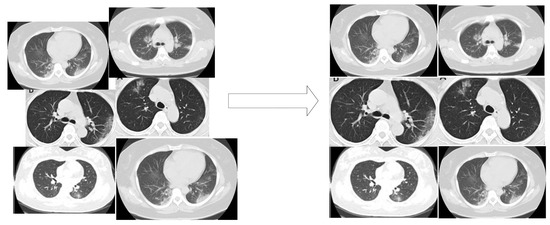

2.3.2. Modified Enhanced Super Resolution GAN Plus (MESRGAN+)

Transition of Super Resolution by GAN

MESRGAN+ Architecture